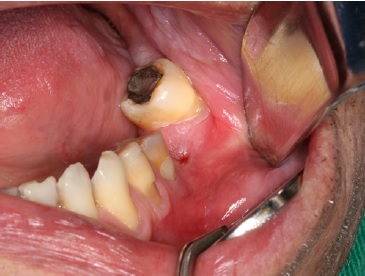

Exame extraoral mostrou ausência de sinais de alterações patológicas. Exame intraoral mostrou ausência do dente 36 e fístula na região de rebordo alveolar, com drenagem de secreção purulenta (Figura 1).

Figura 1 Aspeto clínico intraoral mostrando fístula na região de rebordo alveolar de área edêntula, correspondente ao dente 36.